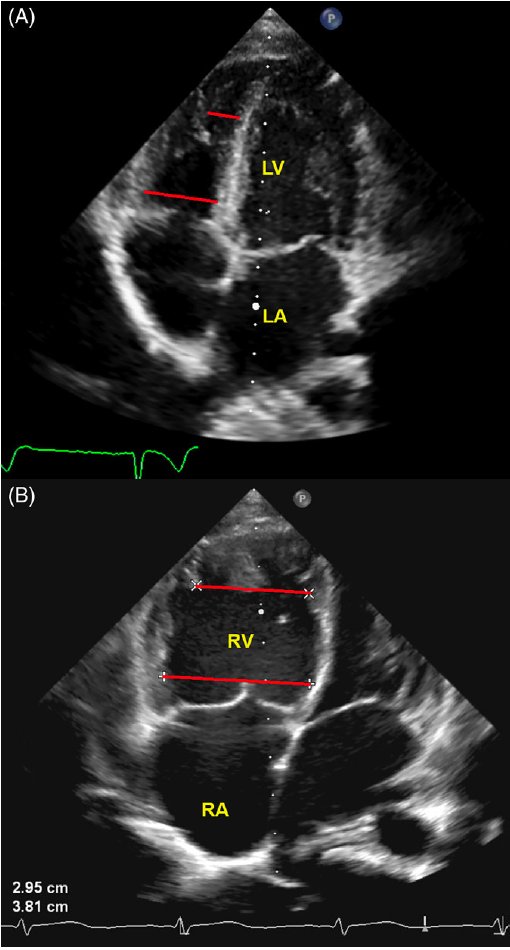

Koestenberger et al.: A decreased right ventricular end-systolic base/apex (RVES b/a) ratio (Fig B) has been shown to be associated with pediatric PAH. Fig. A shows normal RV and LV sizes. Clin Cardiol. 2018; ncbi.nlm.nih.gov/pmc/articles/P… km

Koestenberger et al.: A decreased right ventricular end-systolic base/apex (RVES b/a) ratio (Fig B) has been shown to be associated with pediatric PAH. Fig. A shows normal RV and LV sizes.

Clin Cardiol. 2018; ncbi.nlm.nih.gov/pmc/articles/P…